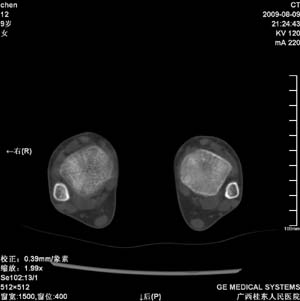

标题: PED2867:右侧内踝肿胀,骨质改变,请各位老师会诊 [打印本页]

标题: PED2867:右侧内踝肿胀,骨质改变,请各位老师会诊

九岁小朋友,近期左侧内踝疼痛,局部肿胀,平时无特殊,近期经常溜干冰

对不起,是右侧内踝肿胀

双踝关节骨质及发育未见异常。